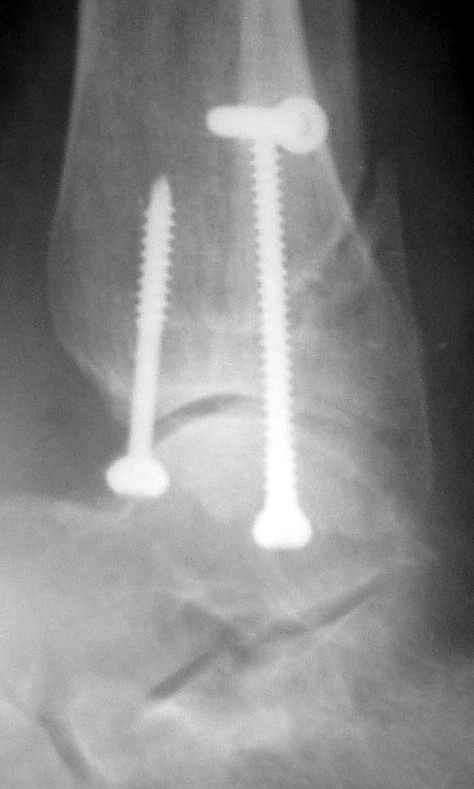

Ниже рентгенограммы

Через месяц

Боковой через месяц

15 ноября прямой

15 ноября боковой

15 ноября трехчетвертной

12 января прямой

12 января боковой

12 января трехчетвертной

Если до сих ничего не сделано, с артродезом сустава в данный момент я бы повременил, на выставленных январских снимках хорошо сохранившийся сустав, а в "мортиз" (трехчетвертной) и на боковых снимках не менее 5 мм укорочение малоберцовой кости. Косые переломы лучше фиксировать пластинами, как то мы разбирали случай, где было отмечено, что это закон "таранная кость всегда следует за малоберцовой".

С подобным случаем приходилось сталкиваться у гормонозависимого пациента с 4 месячным подобным переломом после безуспешного лечения в аппарате Илизарова. Вальгусная стопа, остеопороз, диастаз в медиальной лодыжке. Произвел открытую репозицию мед лодыжки, синтез тяговым винтом 3.5 мм из титана, костную пластику спонгиозой, до 2 см куб из надлодыжечной зоны. Затем остеотомия по линии перелома малоберцовой кости узким долотом из 0.5 см доступа и ручная коррекция вальгуса . Блокирующий винт через обе кости. Остеосинтез по MIPO технологии пластиной 1-3 трубки. Внешней фиксации не применялось, перелом сросся за три месяца. Согласен с д-ром Кульжановым, без пластины в подобных случаях не обойтись.

Делались ли сравнительные снимки, оба сустава в фас на одной пленке? Если с них сделать скиаграммы и наложить их, будет видно, удалось ли устранить наружный подвывих стопы.

Вообще-то начинать надо бы с восстановления длины малоберцовой кости. Вряд ли возможно сделать первой репозицию внутренней лодыжки точно, в таком сроке местных ориентиров нет. Соответственно, смещение внутренней лодыжки кнаружи только уменьшается, но не ликвидируется полностью. Тогда и таран из наружного подвывиха не удается полностью вывести.

тарнная кость находится в латеральном подвывихе, что снижает шансы этого сустава.

Это видно по снимку - середина суставной поверхности тарана должна быть против середины суставной поверхности тибии. Причины, что это не так:

1. Внутренняя лодыжка не на месте

2. наружная лодыжка укорочена

3. Возможно есть компрессионный перелом наружной части пилона тибии.

В подобных случаях лучше всего начинать с главной цели - вправить таран, временно зафиксировать спицами и используя таран как шаблон поставить на место лодыжки, неважно в какой последовательности.